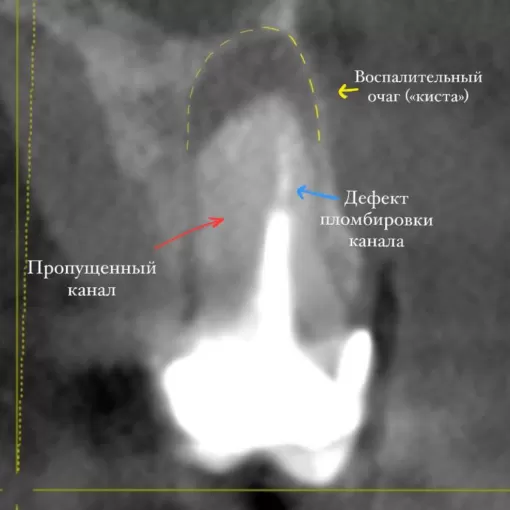

Клинический случай лечения "кисты" зуба 4.7

Стоматолог-терапевт Петрусенко О.А.

Пациент обратился с целью имплантации в области отсутствующего зуба 4.6. Однако после КЛКТ (3Д) исследования был обнаружен воспалительный процесс (киста) в области соседнего зуба 4.7 (рис. 1).